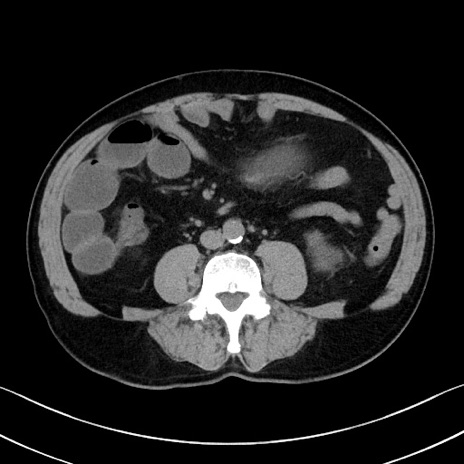

症例35(横断像)

【症例】70歳代 男性

【主訴】腹部膨満、嘔吐

【現病歴】昨日より腹部膨満感出現。本日増悪し、仙痛出現。嘔吐あり、受診。

【既往歴】糖尿病、胆摘後

【身体所見】BP 149/80mmHg、HR 74/min、BT 35.9℃、腹部:膨満、軟、圧痛なし。腸雑音減弱あり。上腹部正中切開瘢痕あり。

【データ】WBC 13500、CRP 1.72